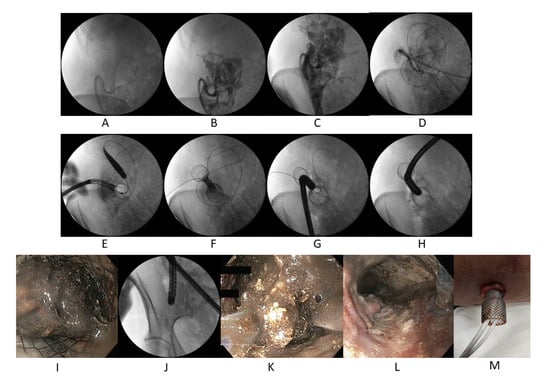

3.4. The Detailed Description of PEN Technique